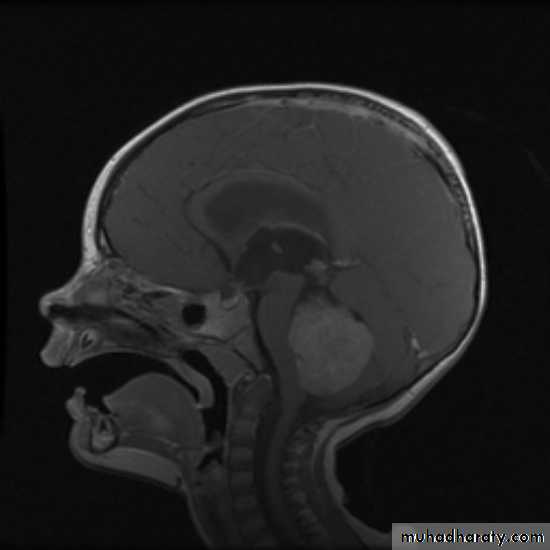

MRIBrain Tumors of Childhood

Histogenesis:* Cell of origin:

glial, neural, primitive, choroid, mixed

* Location:

posterior fossa: 70%

supratentorial: 30%

* Clinical presentation:

location

age

type and grade of the tumor

Symptoms may include:

Increased intracranial pressuresecondary to obstruction of CSF at aqueduct

hydrocephalus (infants), headache, papilledema, vomiting

seizures

focal neurological deficits

hormonal changes (pituitary adenoma)

visual changes (diplopia, field defects)

pressure on optic chiasm